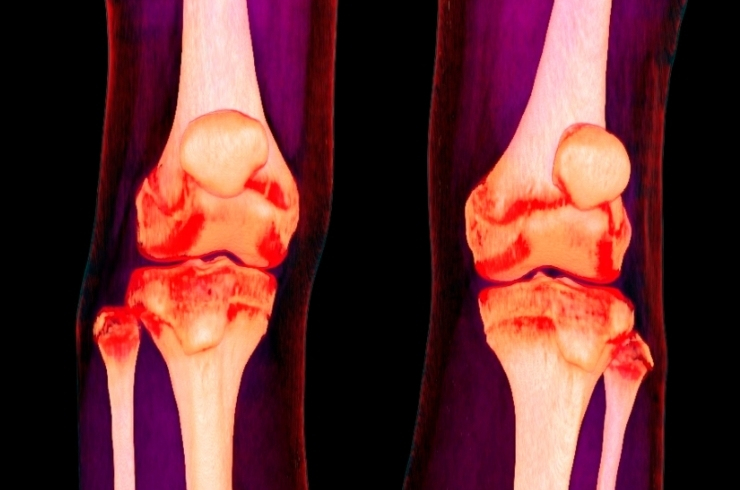

Minimally invasive knee procedures to repair ligaments, restore stability, reduce pain, and enable faster functional recovery.

Advanced techniques to repair meniscus and preserve cartilage, preventing degeneration and maintaining long-term joint health.

Advanced corrective procedures to realign knee joints, reduce pain, delay replacement surgery, and improve long-term joint function effectively and safely for patients.

Innovative procedures to repair damaged cartilage, restore joint surfaces, and improve movement while delaying joint replacement.

Expert evaluation and treatment for knee pain and sports injuries, ensuring faster recovery and safe return.